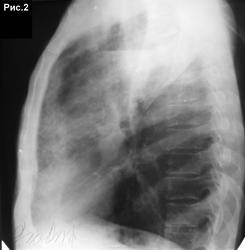

Верхняя доля левого лёгкого инфильтрирована вся. Но негомогенно. Ретростернально инфильтрация интенсивнее. Там, кстати, мне даже мелкие полости чудятся.

слева в сегменте S1+2 определяется уплотнение по типу консолидации ,с нечеткими контурами ,округлыми очертаниями ,которое на боковой соответствует описанным мною сегментам ,с уменьшением объема сегментов(гиповентиляция), формированием кольцевидной тени с горизонтальным уровнем жидкости(высвобождение содержимого в бронх) ,прилежащим к костальной плевре .также в S4 слева определяется уплотнение по типу инфильтрации небольших размеров ,с размазанными контурами.диагноз:согласен с Петровичем+добавлю первичный механизм формирования абсцесса, стадия нероза с распадом и формированием кольцевидной тени,инфильтрация в S4

Походу полость то не маленькая, на боковушке уровень широкий!